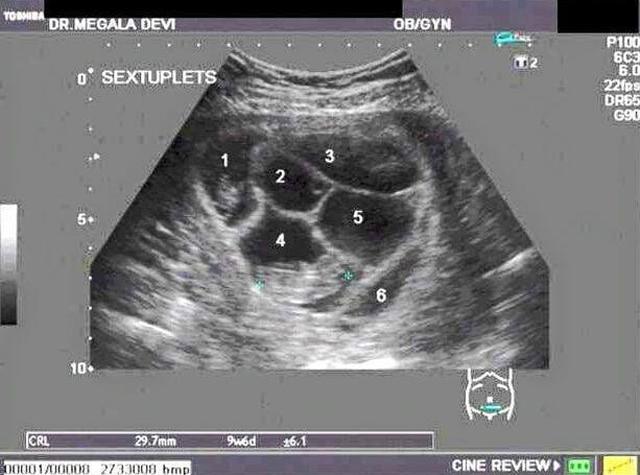

Thế nhưng đó chưa phải là tất cả, khi chị Lauren đi siêu âm, các bác sĩ đã vô cùng sốc khi biết chị không chỉ mang 1 mà là 6 đứa trẻ trong bụng. Phôi thai đã tách ra làm 6 và tỷ lệ này là vô cùng hiếm khiến ai nấy đều ngạc nhiên.